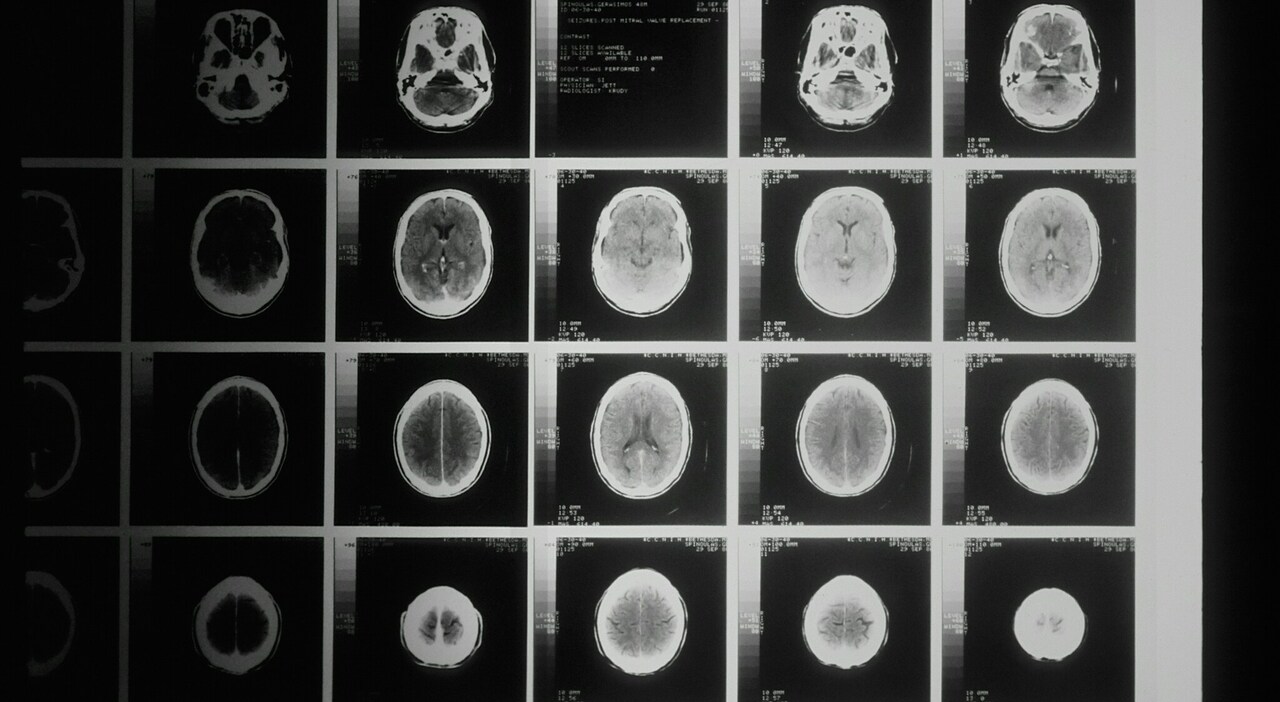

Il glioblastoma rappresenta una delle forme più aggressive di tumore cerebrale, caratterizzandosi per una elevata difficoltà di trattamento. Questo tipo di tumore, noto per la sua resistenza alle terapie immunologiche, ha spinto gli scienziati a cercare nuove strategie terapeutiche. Recentemente, un team dell’Istituto Neurologico di Milano, diretto dalla dott.ssa Serena Pellegatta, ha made significant strides nella lotta contro questa malattia devastante. Lo studio, pubblicato sulla rivista Nature Communications, propone un approccio innovativo utilizzando i linfociti T (un tipo di cellula del sistema immunitario) dei pazienti.

Lo studio effettuato presso l’Istituto Neurologico di Milano ha coinvolto 161 pazienti con diagnosi di glioma diffuso. I linfociti T potenziati sono stati testati su modelli animali e i risultati sono stati incoraggianti. Infatti, si è osservato un rallentamento della crescita tumorale nel 70% dei casi, insieme a un aumento della sopravvivenza dei soggetti trattati. Questo progresso segna un importante passo avanti nella ricerca sul glioblastoma, con il protocollo che ha già passato la verifica secondo gli standard Good Manufacturing Practices (GMP), necessari per il suo uso clinico.